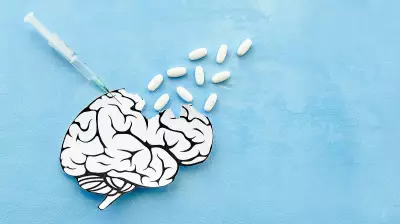

Health